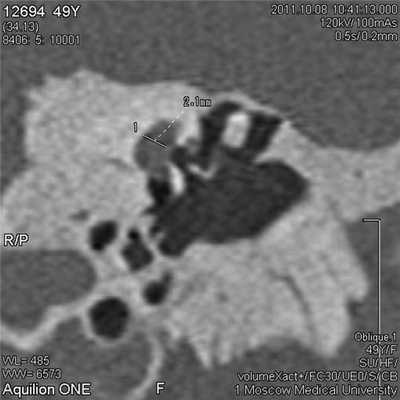

Особое внимание обращали на наличие дефектов костной стенки фаллопиева канала и, как следствие, протрузий лицевого нерва в просвет ниши окна преддверия. Оценить степень нависания промонториальной стенки можно по ширине угла между основанием стремени и линией, проведенной вдоль промонториума в точке его максимального выпячивания в косой проекции. Кроме того, определяли соотношение между основанием стремени и структурами внутреннего уха (маточкой и сферическим мешочком), измеряя расстояние от середины основания стремени (перпендикулярно) до медиальной стенки преддверия (рис. 3). Рисунок 3. МСКТ височной кости, косая проекция. Пациент Д., 49 лет. Расстояние между подножной пластиной стремени и внутренней стенкой преддверия равно 2,1 мм.